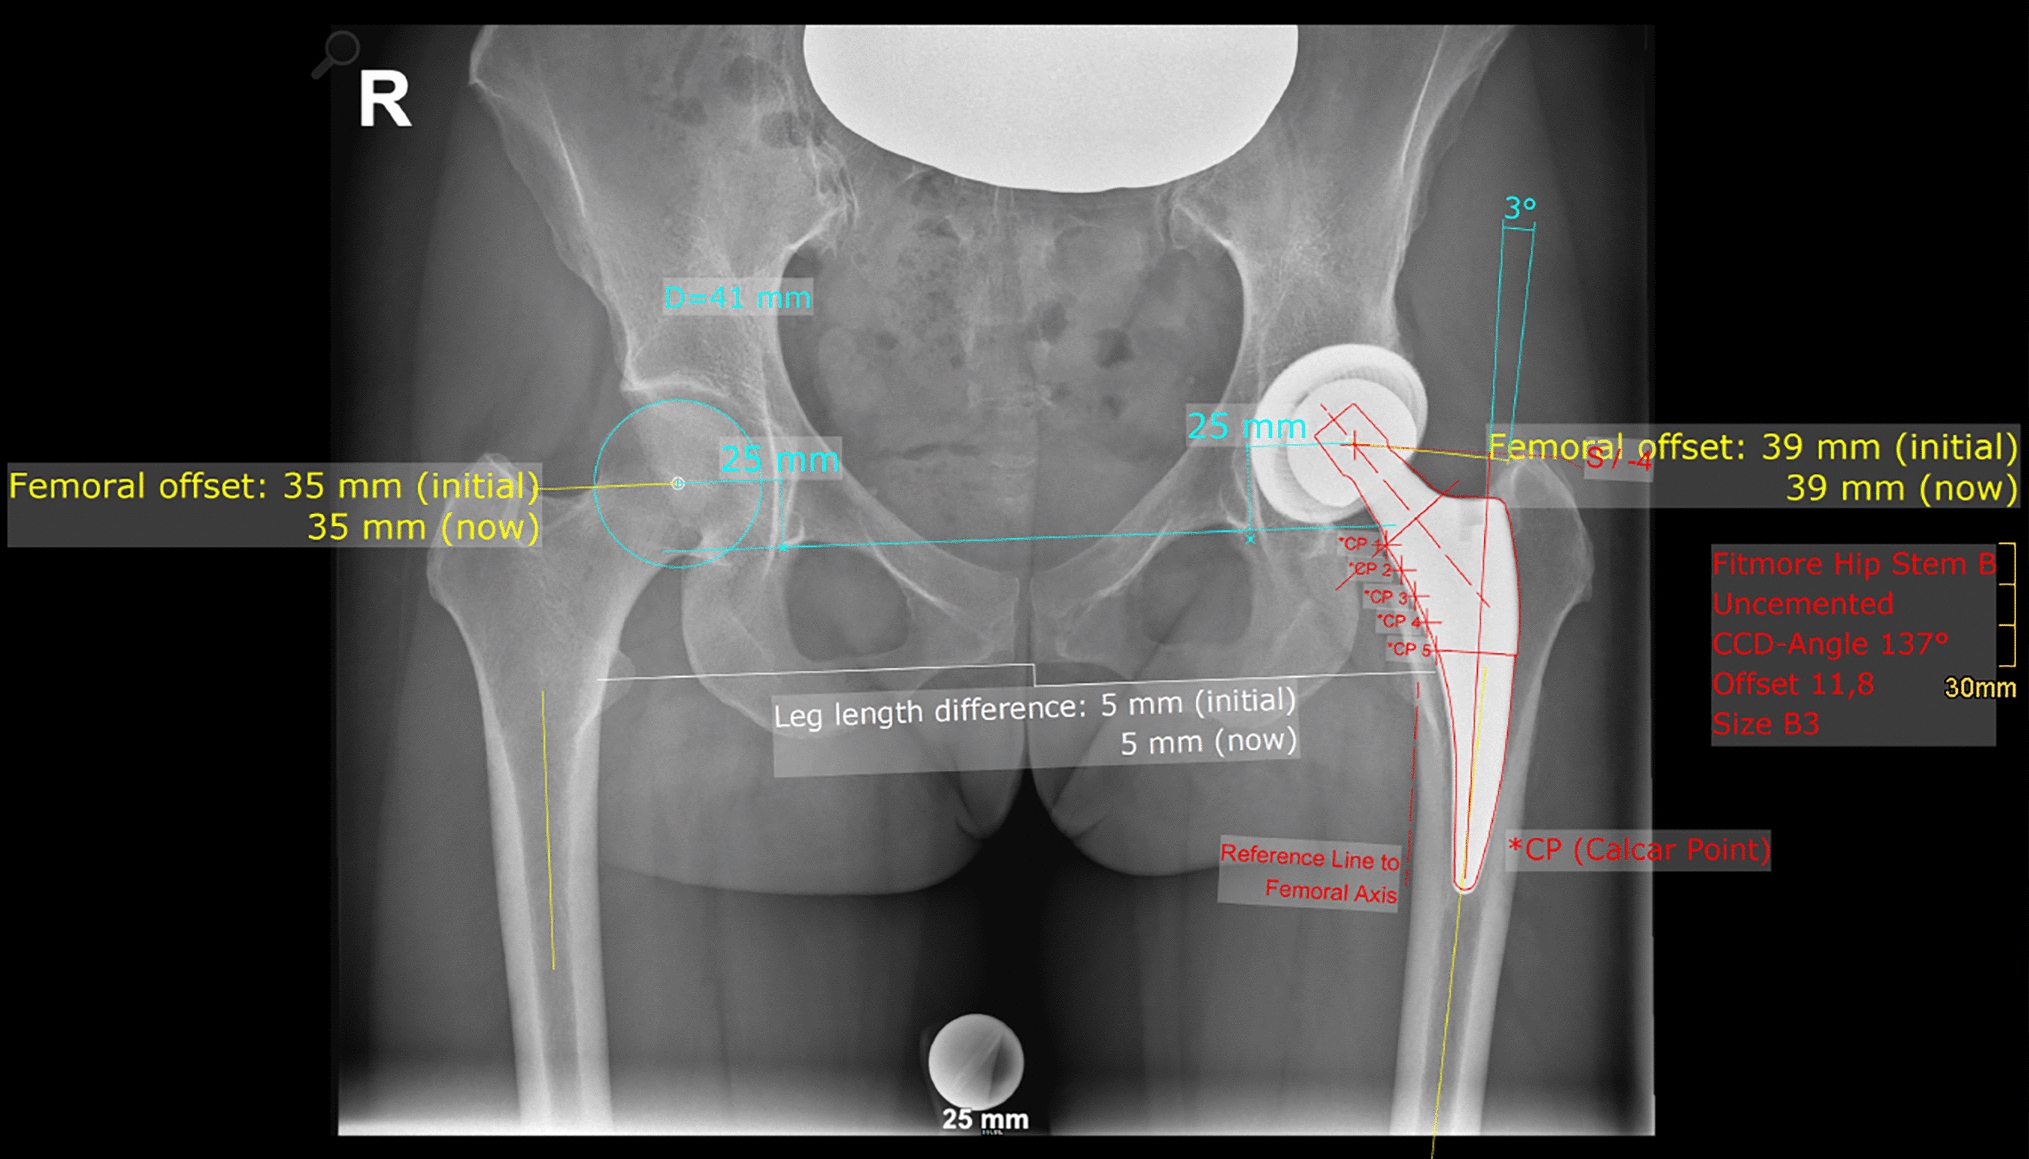

Radiographic measurement was performed on preoperative and 3 months postoperative digital low-centered AP radiographs of the pelvis [17]. Measurements were conducted independently by two reviewers (M.L., J.A.), who were not involved in the index surgery. Radiographs were taken with the patient in standing position and with both legs in 15° internal rotation with the central beam directed on the symphysis pubis [18]. To achieve an accurate measurement of the hip anatomy a double coordinate system was applied on both the preoperative and the postoperative images [1, 19]. Radiographic analysis was performed using MediCAD® Software V5.1 (Hectec GmbH, Germany). The hip center of rotation (COR) was defined using a circle tool determining the diameter of the femoral head and its center [20]. The femoral offset (FO) was determined as the perpendicular distance between the COR and the proximal femoral shaft axis (FSA) [17, 20]. Acetabular offset (AO) was measured as the perpendicular distance between the COR and line T, with T being the perpendicular line on the transteardrop line (TT) through the ipsilateral teardrop figure [17]. Hip offset (HO) was calculated as the sum of FO and AO [17]. The vertical position of the COR was measured as the perpendicular distance to line TT [21]. Radiographic leg length discrepancy (LLD) was measured as the perpendicular distance between line TT and the middle of the lesser trochanter (LT) [18]. Centrum–collum–diaphyseal (CCD) angle was determined according to M. E. Müller on the affected hip [22]. Definition of the stem axis of the implanted cementless stem was previously described for cementless straight stem [23] and for Fitmore® hip stem [24]. For enabling exact measurement of the stem axis of the implanted Fitmore® stem, a digital template of the stem size was put over the implanted stem on the postoperative X-ray. The templating software displayed the correct stem axis of the implanted Fitmore® hip stem, Fig. 3. The critical trochanter angle (CTA) was measured as described by Haversath et al. [7]. The angle crest is defined as the intersection of the femoral shaft axis and the femoral neck axis. A leg between the angle crest and the trochanter vertex is built, and the CTA is measured between this leg and the femoral shaft axis, Fig. 1. To characterize the anatomical shape of the proximal femur and the thickness of cortical bone, the canal to calcar isthmus ratio and the cortical index (CI) according to Dorr et al. [25] were determined. A high CI indicates a thick cortical bone [25]. Additionally, the canal flare according to Noble et al. [26] was determined. The stem alignment was measured as the difference in degrees between the anatomic femoral shaft axis and the vertical stem axis [27]. On preoperative X-rays FO, AO, HO and LLD were measured bilaterally, while CCD angle, CI, Canal Flare Index and canal to calcar ratio were measured unilaterally on the affected hip. Complete preoperative measurements are also shown in Fig. 2.

On postoperative X-rays FO, AO, HO and LLD were measured bilaterally, while stem alignment was measured unilaterally on the operated hip. Complete postoperative measurements are also shown in Fig. 3.

Fig. 3

Postoperative measurements: HO, FO, AO, LLD (all bilaterally), stem alignment (unilaterally)

Bild vergrößern